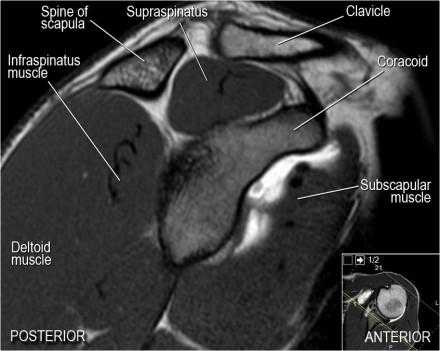

Нормальная сагиттальная анатомия и контрольный список

- обратите внимание на мышцы манжеты вращателей и поищите их атрофию

- обратите внимание на среднюю плече-лопаточную связку, которая имеет косое направление в полости сустава, и изучите отношение к сухожилию подлопаточной мышцы

- на данном уровне иногда видны повреждения суставной губы в направлении на 3-6 часов

- изучите место прикрепления длинной головки двуглавой мышцы плеча к суставной губе (biceps anchor)

- обратите внимание на форму акромиона

- поищите импинджмент за счет акромиально ключичного сустава. Обратите внимание на интервал между мажетой вращателей и клювовидно-плечевой связкой (coracohumeral ligament).

- поищите повреждение подостной мышцы